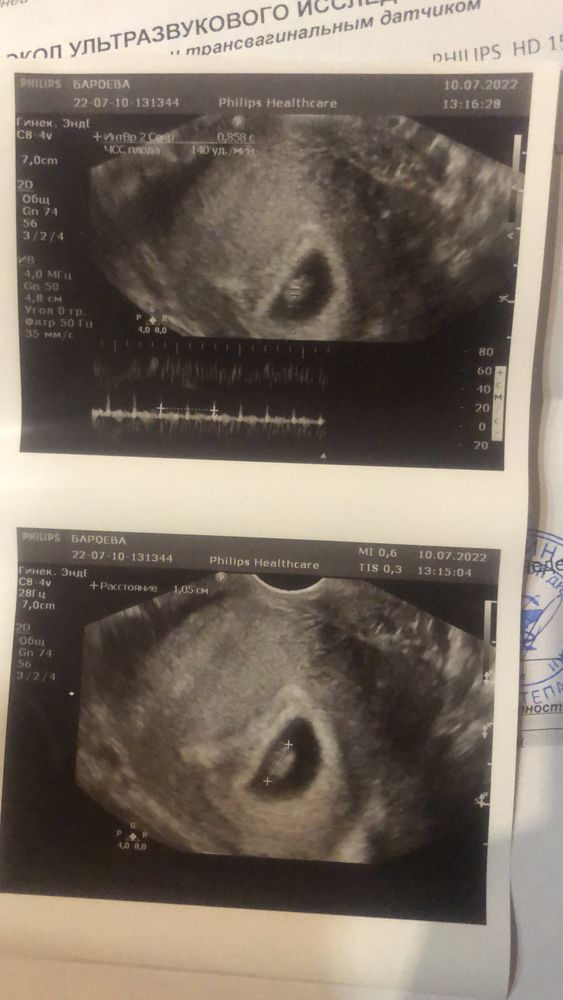

Изображение 7,2

Nazira Khairullina, тут 0,8см

Nazira Khairullina, 1 см

Изображение 7 недель и 1 день

Изображение 7 ровно

Изображение Тут без одного дня 7 недель

Изображение Срок 7 недель, ктр 0.53 см. Соответствует сроку 6 и 2 дня.